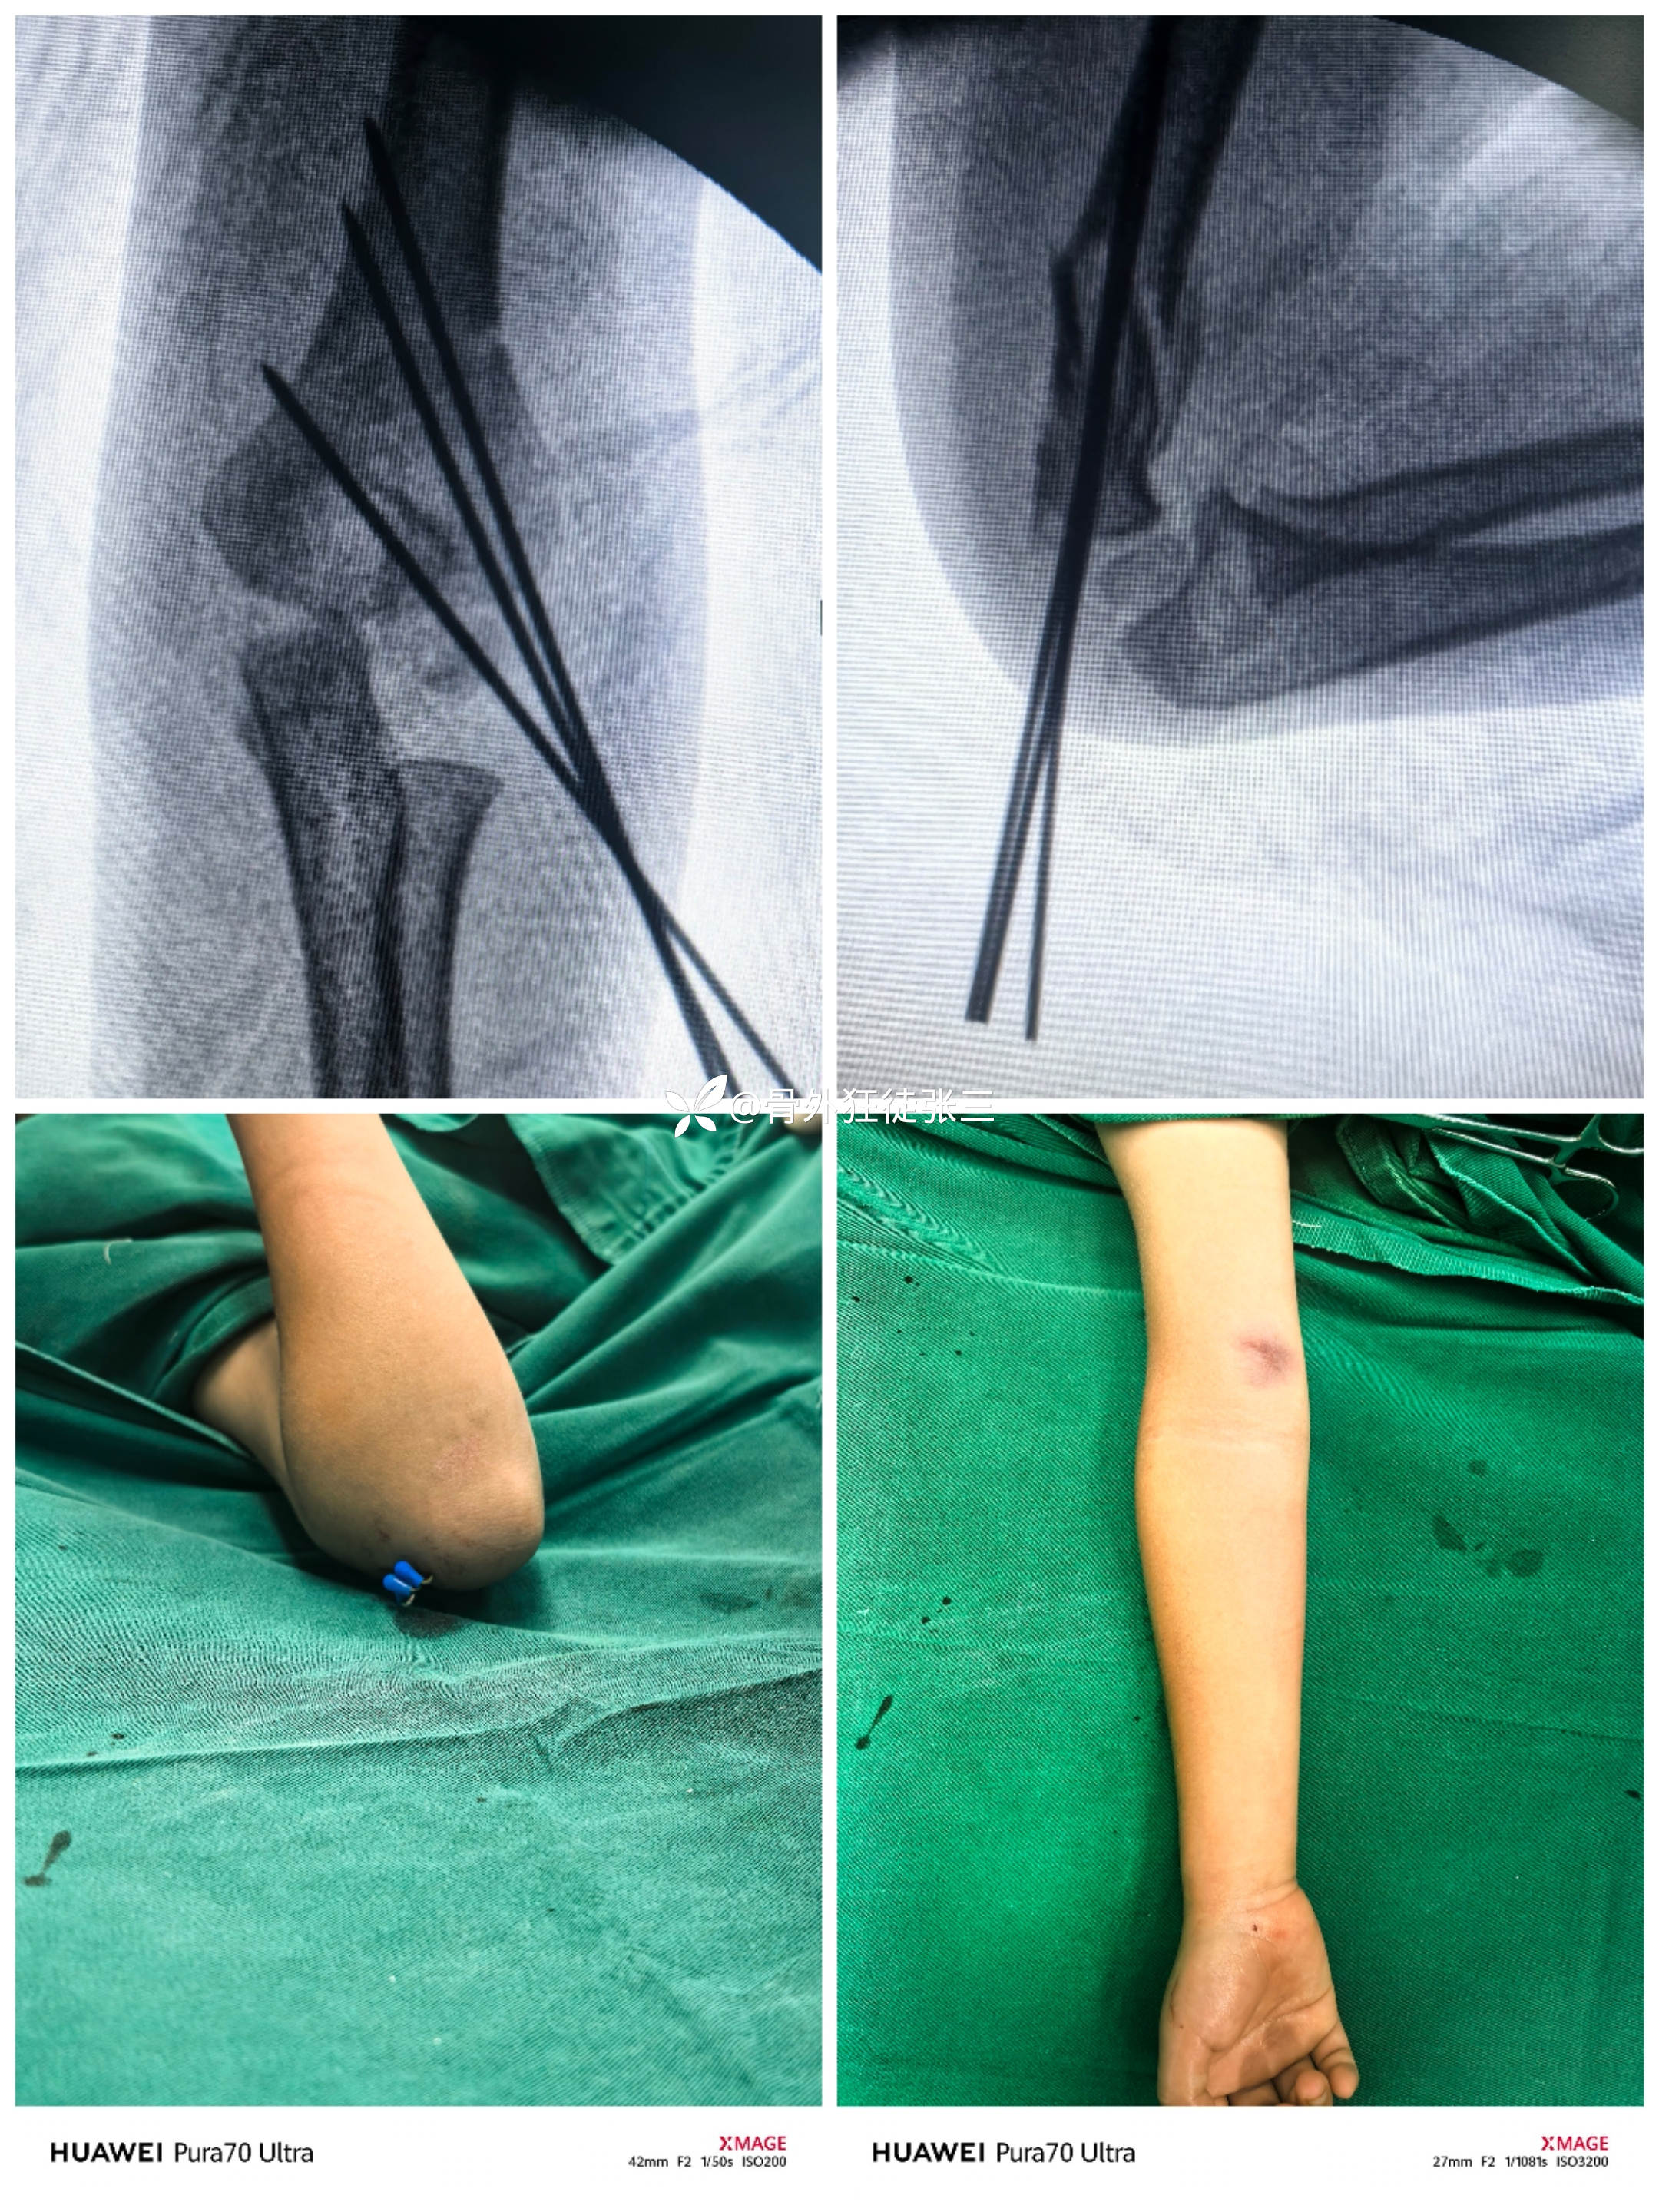

术后影像:

术前术后对比:

1次复位,6次透视,5分钟搞定

左手维持复位,右手穿针,助手帮忙上电钻

1,手法复位:旋后——牵引——屈肘。

2,保持过度屈曲,外侧穿针2枚,透视侧位,正位。

3,穿第三枚针,透视正侧位。

4,根据情况,必要时调整克氏针方向,尽量做到发散固定。(本例克氏针分散不完美,骨折牢固,没有调整,不愿意再损伤)